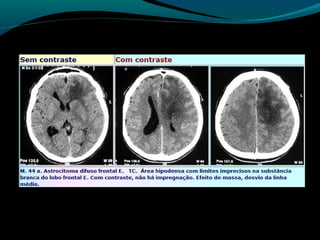

Astrocitoma difuso (GRAU II OMS)

Bem diferenciado;

Grau II;

10 a 15% dos astrocitomas;

Entre 20 a 45 anos;

Crescimento lento;

Tendência para degeneração maligna;

2/3 supratentoriais (frontal e temporal);

Convulsão e cefaléia;

Grau II, tendência à progressão para astrocitoma

anaplásico;

TC:

lesão hipo ou isodensa;

Geralmente NÃO se impregna por contraste ( se sim,

pensar em degeneração maligna);

RM:

Aspecto aparentemente circunscrito mas tumor se

infiltra;

Hipointenso em T1 e hiper em T2 e FLAIR;

Realce pelo Gd no tumor ou leptomeninge  pensar em

degeneração maligna;